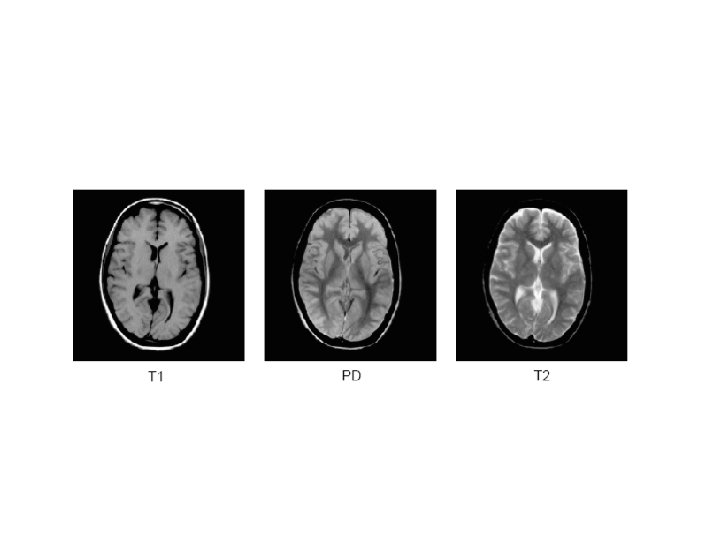

Relaxation • T 1 Relaxation: – releasing the absorbed energy in the shape of (very little) warmth and RF waves. – T 1 relaxation is also known as Spin-Lattice relaxation, because the energy is released to the surrounding tissue (lattice).

T 1 • One H atom may be bound very tight, such as in fat tissue, while the other has a much looser bond, such as in water. Tightly bound protons will release their energy much quicker to their surroundings than protons, which are bound loosely. The rate at which they release their energy is therefore different.

• Each tissue will release energy (relax) at a different rate and that’s why MRI has such good contrast resolution.

T 2 Relaxation • First of all, it is very important to realize that T 1 and T 2 relaxation are two independent processes. The one has nothing to do with the other. The only thing they have in common is that both processes happen simultaneously. T 1 relaxation describes what happens in the Z direction, while T 2 relaxation describes what happens in the X-Y plane.

• This process of getting from a total inphase situation to a total out-of-phase situation is called T 2 relaxation. • Fat tissue will de-phase quickly, while water will de-phase much slower.

• T 2 relaxation happens in tens of milliseconds, while T 1 can take up to seconds.